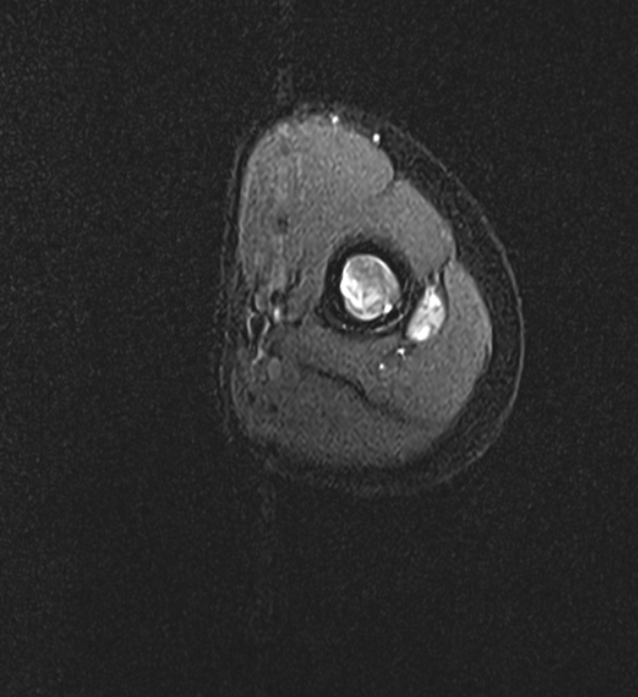

A 39 year old female presented with lower back pain and leg pain since 3 months.